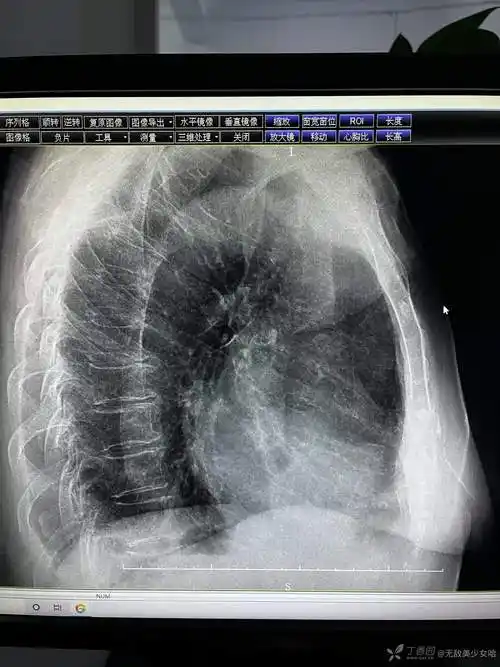

心包积液还是脂肪垫他这个胸片怎么描述合适

疑难问题,看看这张胸片